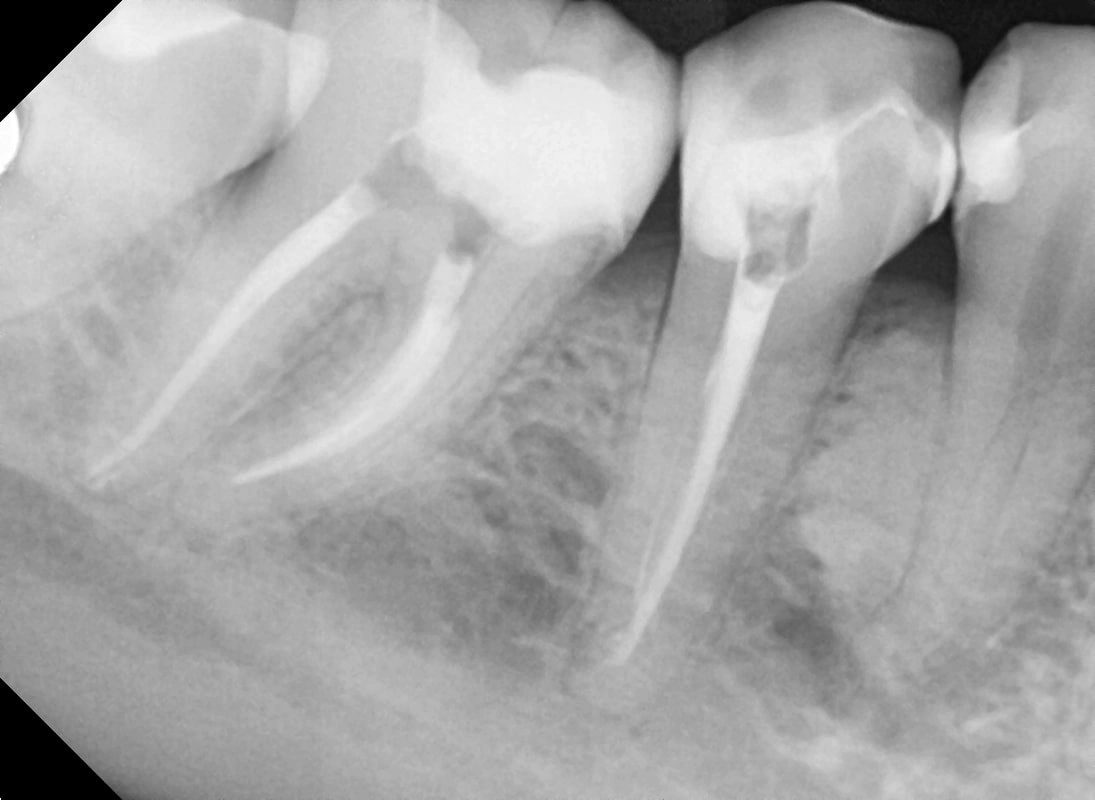

Прицільний знімок зубів

Прицільний знімок зубів – це локальний знімок 1-3 зубів, який проводять за допомогою цифрового рентгенологічного апарата (радіовізіографа). Він є найпростішим і найпоширенішим методом діагностики в стоматології.

карієсу – знімок дозволяє виявити каріозні ураження під пломбою або протезом

пульпіту – лікар оцінює стан зубних коренів, визначає кількість каналів

перикороніту – для уточнення положення зуба

гранульоми, кісти або травми зуба

• хороша деталізація структур зуба і навколозубних тканин